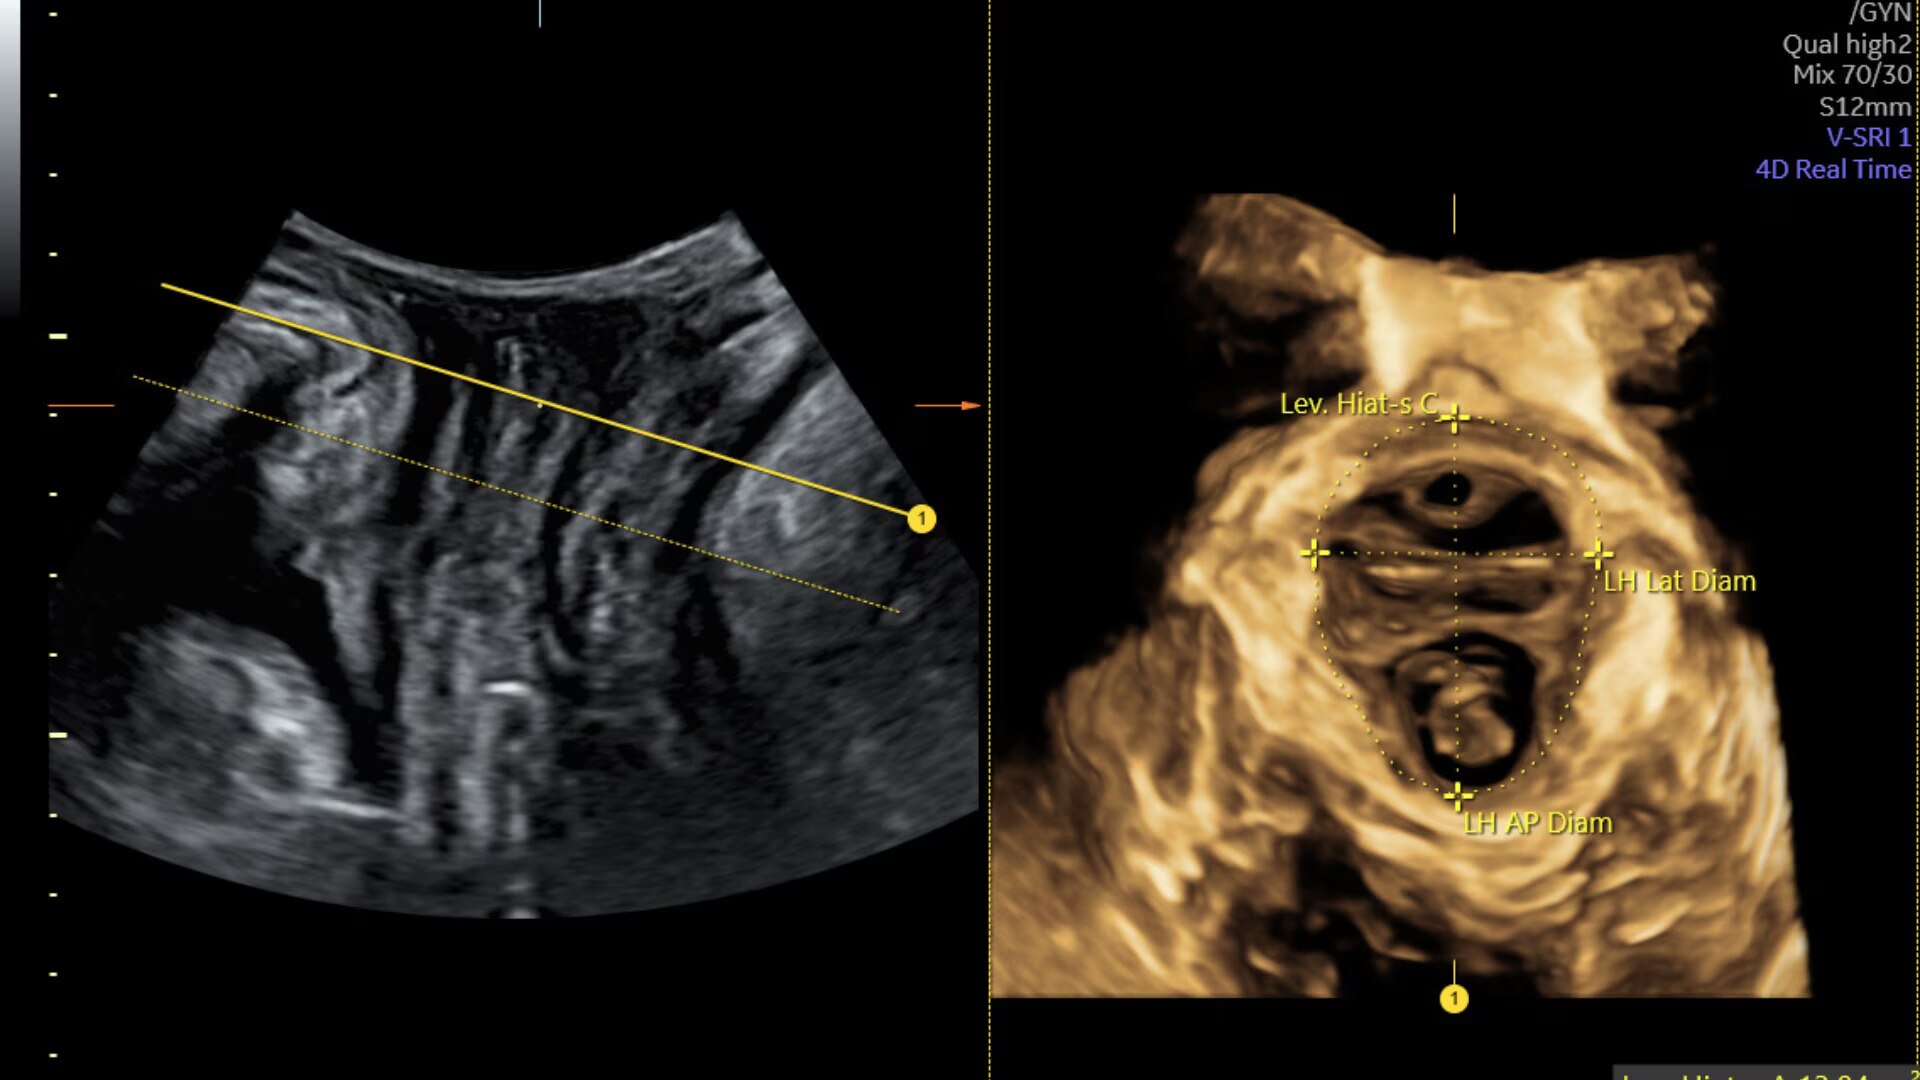

Assess pelvic floor anatomy using guided workflow & AI

Using a guided workflow and AI, SonoPelvicFloor:

• removed exam complexity by automating plane alignment and measurements

• can reduce keystrokes by up to 75% and offer users a time savings of up to 80%